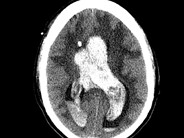

Massive intraventricular hemorrhage in a patient with Ph+ ALL undergoing chemotherapy. The tip of an Ommaya catheter is noted in the right frontal horn of the lateral ventricle.